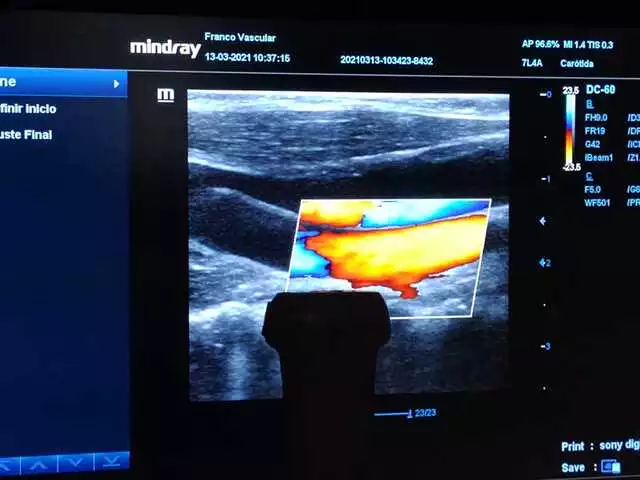

Doppler de vasos abdominales y pélvicos

El doppler de vasos abdominales y/o pélvicos permite establecer la presencia de zonas con deficiente circulación en las arterias del abdomen, además permite establecer la presencia de aneurismas en esta localización.

Se indica en pacientes con dolor abdominal luego de las comidas asociado a pérdida de peso.

Para este estudio se requiere un ayuno de 6 horas.